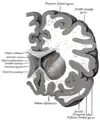

Transverse Cut of Brain (Horizontal Section), basal ganglia is blue

This is a transverse view of the caudate nucleus from a structural MR image.

Transverse view of the caudate nucleus from a structural MR image